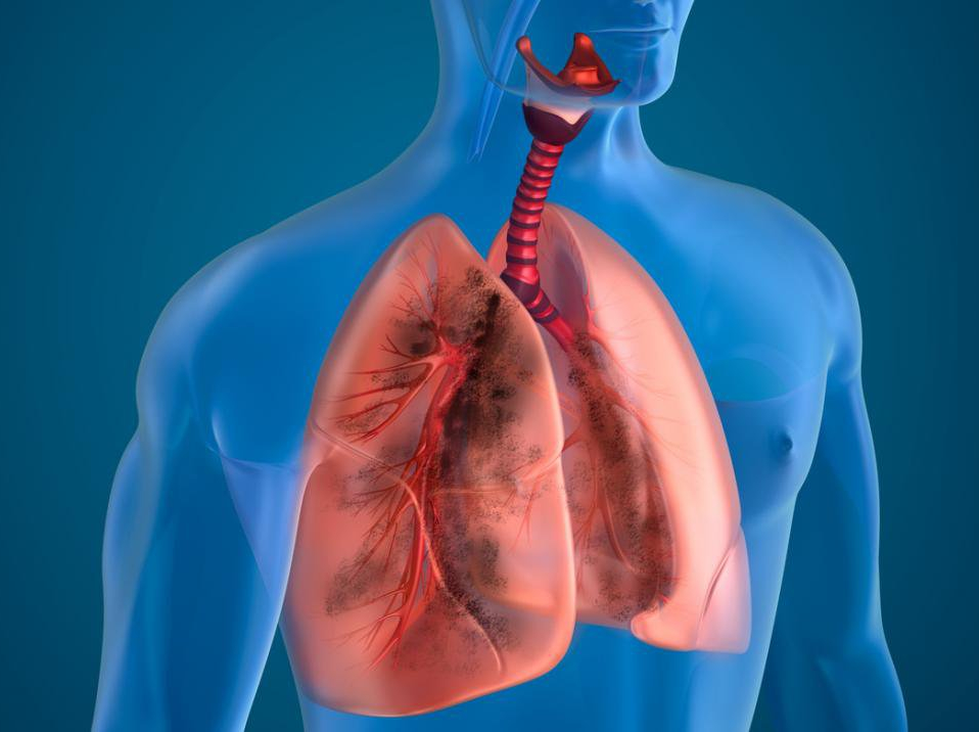

Phổi tắc nghẽn mạn tính là gì?

Bệnh phổi tắc nghẽn mạn tính là bệnh lý hô hấp mạn tính có đặc trưng bởi sự tắc nghẽn luồng khí thở ra không hồi phục hoàn toàn, sự cản trở thông khí này thường tiến triển từ từ và liên quan đến phản ứng viêm bất thường của phổi với các phân tử hoặc khí độc hại, trong đó khói thuốc đóng vai trò hàng đầu. Bệnh phổi tắc nghẽn mạn tính là một bệnh ngừa được và điều trị được với một số hậu quả ngoài phổi có thể góp phần vào độ nặng của từng bệnh nhân.